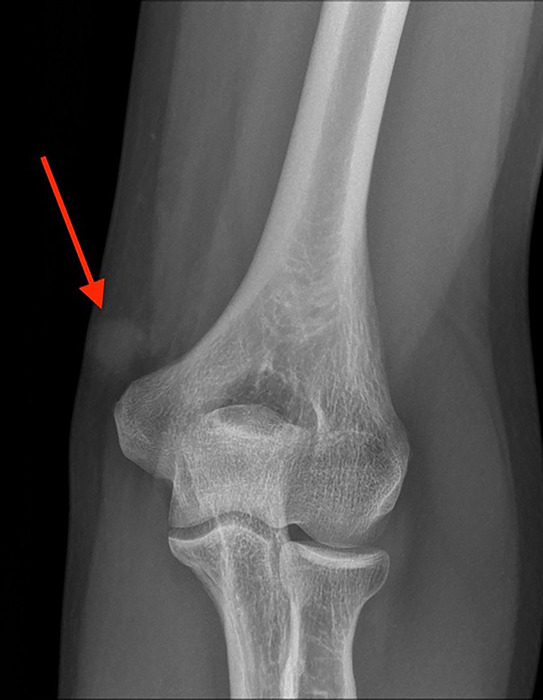

Extradigital Glomus Tumor at the Elbow.

Teaching point: Extradigital glomus tumor should be considered in the differential diagnosis of a highly vascular solid lesion that is painful on palpation.